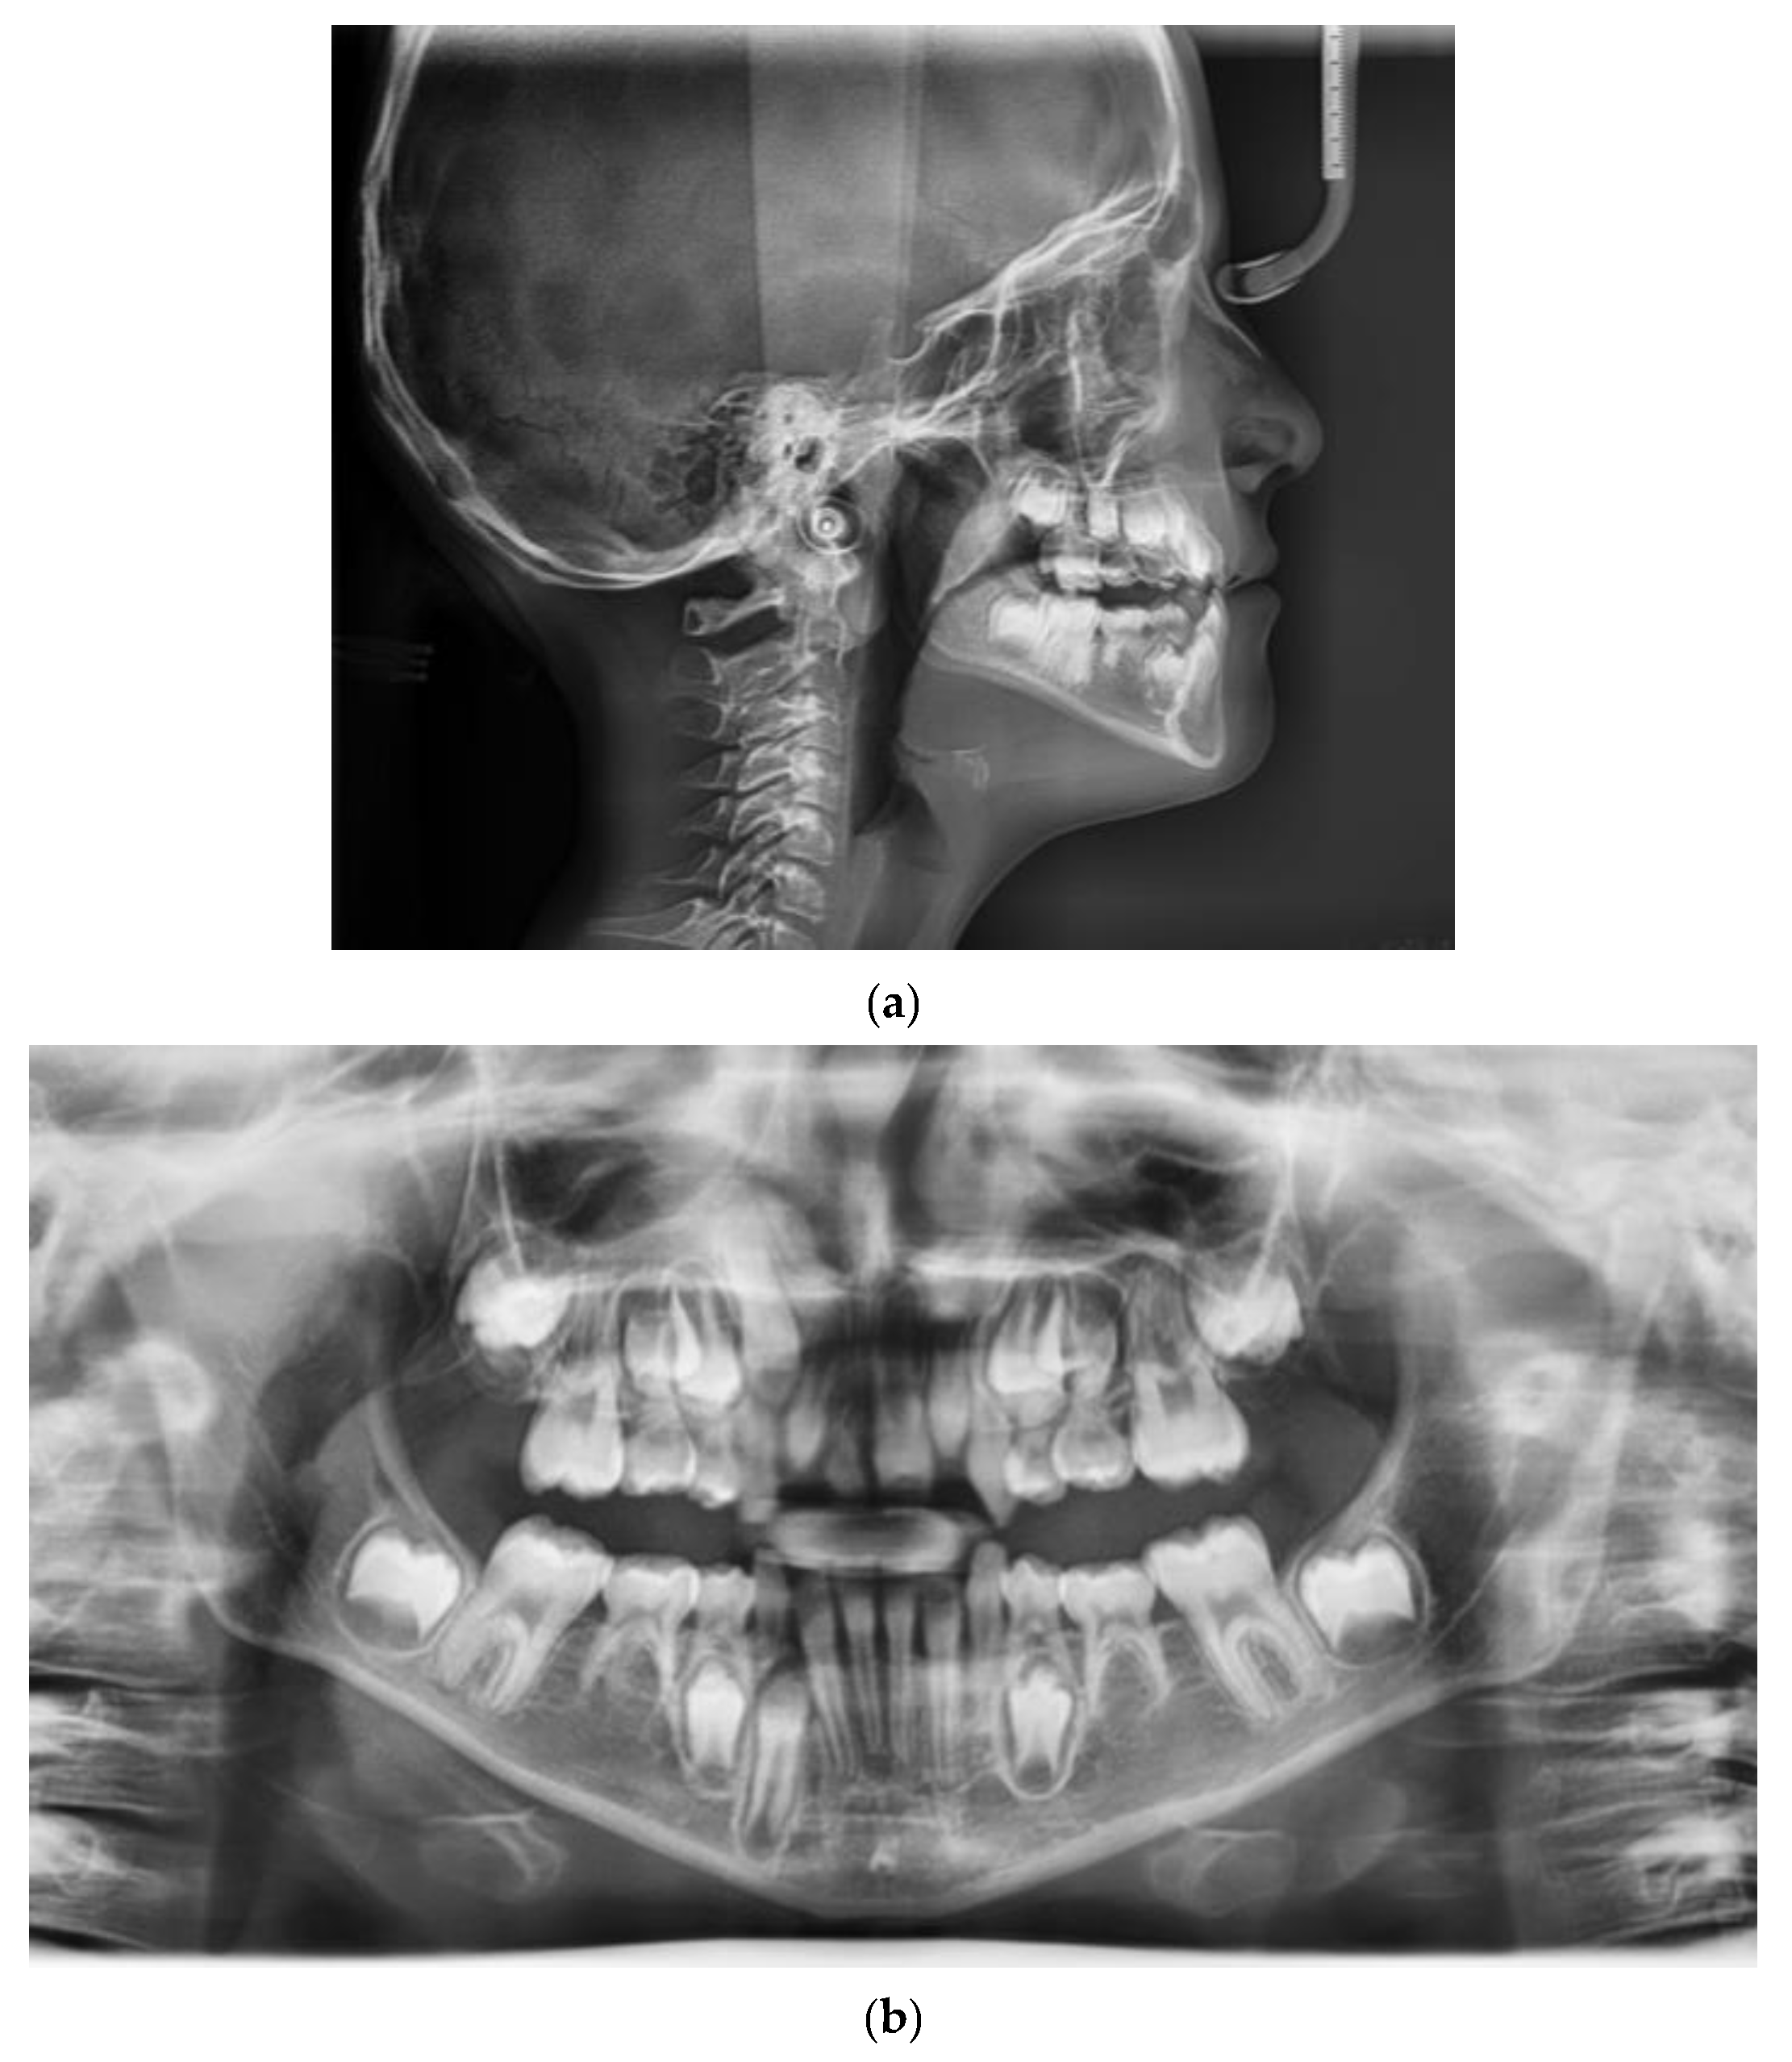

5. Results

| Pretreatment | Post-Treatment | |

|---|---|---|

| Sagittal Skeletal Relations | ||

| SNA | 75.8° | 76.4° |

| SNB | 79° | 77° |

| ANB | −3.2° | −1.6° |

| Wits | −8 mm | −4 mm |

| Vertical Skeletal Relations | ||

| SN/ANS-PNS | 9.2° | 12.2° |

| SN/Go-Gn | 40° | 40° |

| ANS-PNS/GoGn | 30° | 28° |

| Dento-Basal Relations | ||

| I/ANS-PNS | - | 110.5° |

| i/GoGn | - | 75° |

| i/APg | - | +3.3 mm |

| Dental Relations | ||

| Overjet | −1 mm | +1.2 mm |

| Overbite | - | +0.3 mm |

| Interincisal Angle | - | 154.8° |

| Linear measurements | ||

| Maxillary length | 38.8 mm | 40 mm |

| Mandibular length | 60 mm | 62 mm |